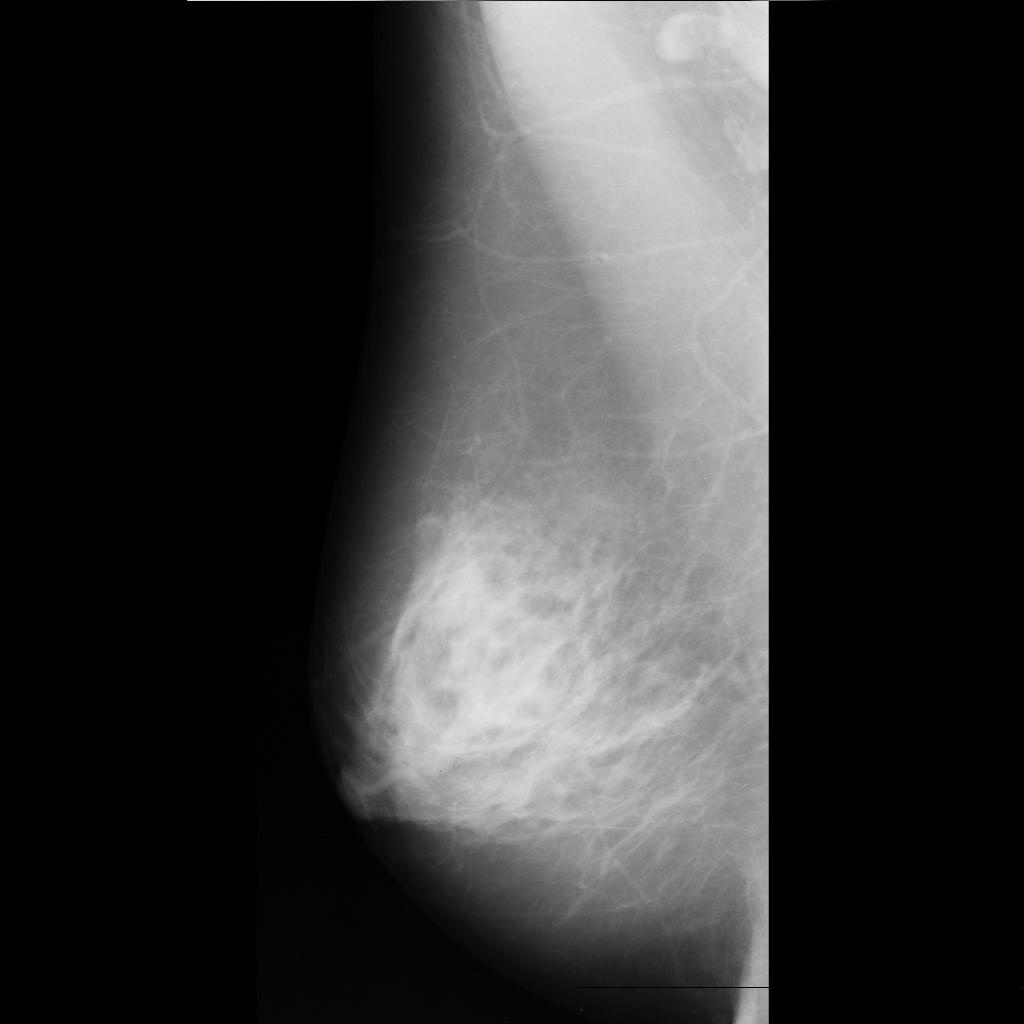

malignant